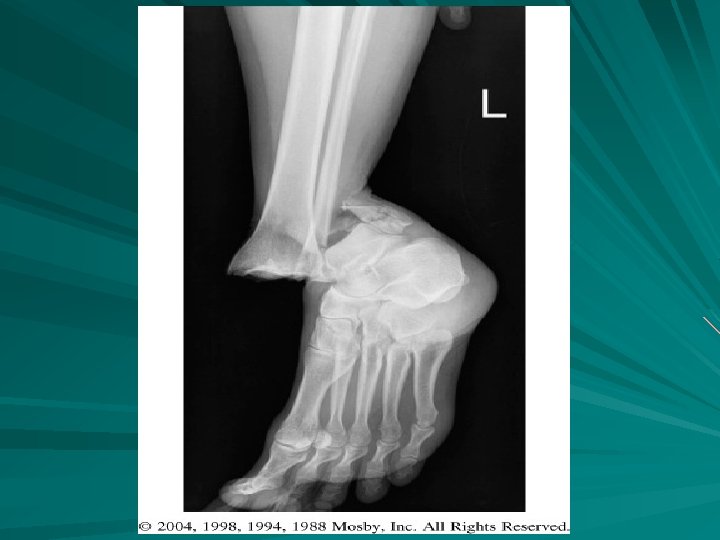

FX RADIAL HEAD